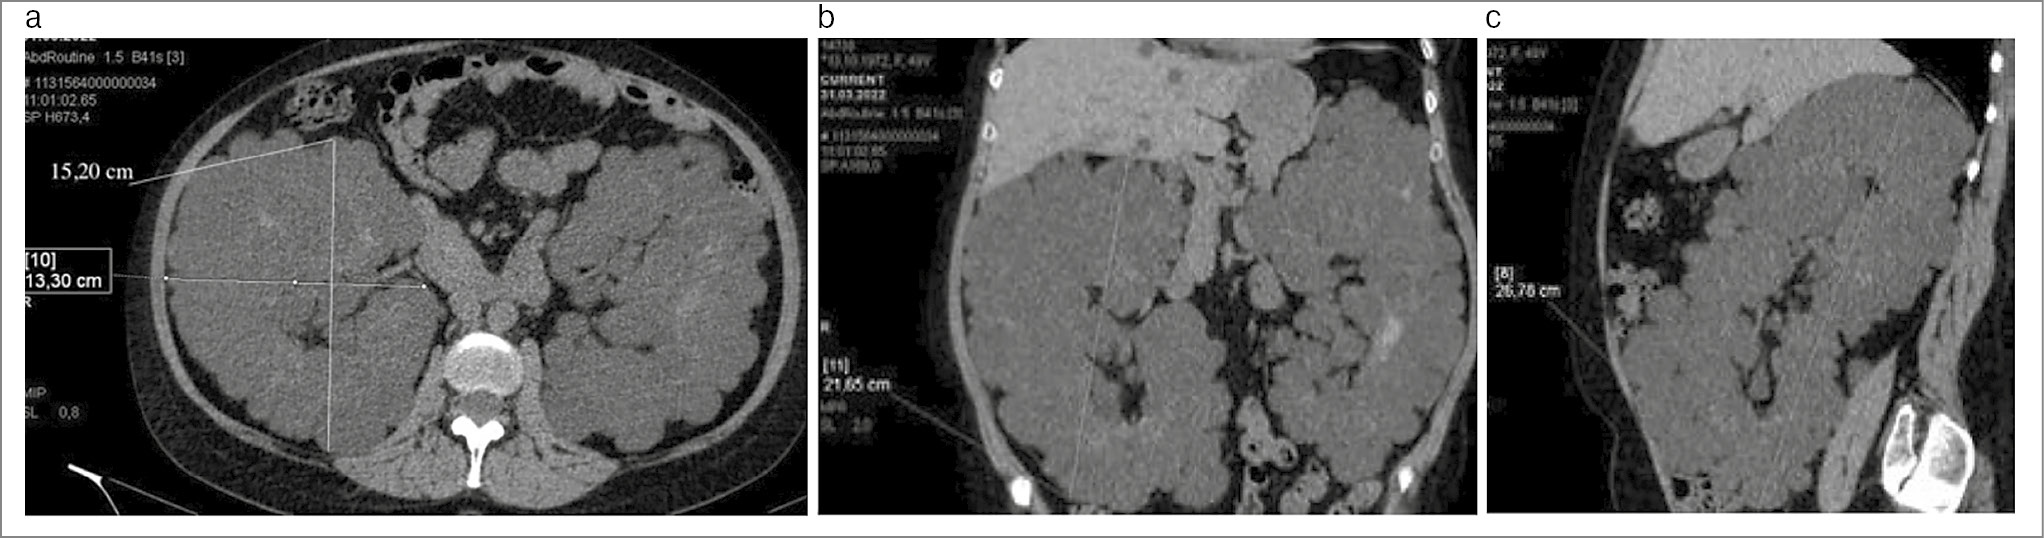

Всем пациентам проведены предоперационное обследование сопутствующей патологии с определением анестезиологических рисков и мультиспиральная компьютерная томография с контрастным усилением для оценки ангиоархитектоники почечной ножки и определения размеров почки. При измерении почки определяли объем по формуле эллипсоида, для подсчета которого необходимо получение трех размеров в разных плоскостях: передне-заднего, поперечного и краниокаудального (рис. 2).

Рис. 2. Мультиспиральная компьютерная томография почек с определением объема поликистозной почки: a – аксиллярная проекция; b – прямая проекция; c– сагиттальная проекция.

Средний объем удаляемых почек составил 3138,74±356,30 мл, при этом фиксировано, что у всех пациентов правая почка была несколько меньше левой (3030,79±339,16 и 3246,68±373,46 мл соответственно). Склонность к артериальной гипертензии до операции отмечали большинство (76%) пациентов на фоне приема корригирующей терапии. Систолическое артериальное давление до операции составило 144,37±9,68 мм рт. ст., пульсовое – 57,5±10,29 мм рт. ст. Подавляющее число пациентов имели склонность к анемии: уровень гемоглобина до операции был 113,8±13,1 г/л.